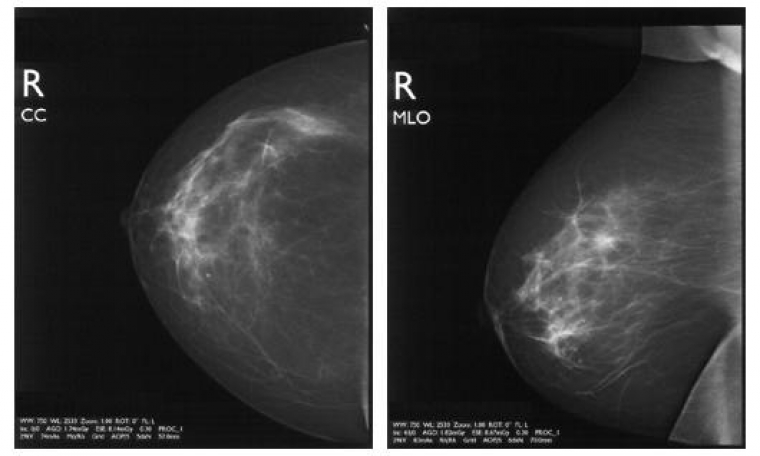

Particularité radiologique du sein

Le sein est un organe constitué de tissus mous. Il comporte des éléments hydriques (peau en surface, tissus glandulaires et conjonctifs en profondeur), des éléments graisseux (qui sont à l'origine du contraste radiologique) et des calcifications (dépôts calciques dans la fibrose, la nécrose, les parois vasculaires, la concentration de sécrétions glandulaires.) Les éléments hydriques et graisseux n’ont pas une grande différence d’atténuation, aussi les différences de contrastes sont faibles, or en mammographie, l’utilisation de produits de contraste reste limité à quelques cas très particuliers (exploration d’un canal galactophore par injection dans ce canal d’un produit à base d’iode, Figure 4). Pour obtenir un contraste suffisant, il est donc nécessaire que les rayons X ne soient pas trop perforants, c'est-à-dire utiliser un faible kilovoltage (typiquement entre 25 et 30 kV, contre souvent plus de 100 pour d’autres types de radiographie). L’information d’une mammographie est donc essentiellement contenue dans les nuances de gris (Figure 5), et il est essentiel que le film ne soit pas sur ou sous-exposé. Une bonne mammographie repose sur des choix judicieux (matériel, film, développement, etc…) et surtout sur l’expérience du radiologue. Une des difficultés de la lecture d’une mammographie provient du fait qu’un sein n’est pratiquement jamais dépourvu de diverses marques du passé (fibroses, kystes, opacités diverses) qui peuvent compliquer l’interprétation, quand ce n’est pas masquer un élément pathologique puisque les différents éléments se superposent sur le cliché. D’où, entre autre, l’intérêt de réaliser plusieurs clichés sous différents angles, et de comparer l’image radiologique des deux seins.

Les principales pathologies du sein et leur traduction radiologique

Le cancer est loin d’être la seule pathologie du sein, même si elle reste la plus grave. Dans la majorité des cas, heureusement, les anomalies détectées se révèlent être des tumeurs bénignes, des fibroses ou des kystes. Toutes ces anomalies, malignes ou bénignes, ont pour caractéristique d’apparaître comme des structures hydriques (présence de liquide ou amas fibreux), correspondant à des zones assez claires en radiographie au contraire des éléments graisseux qui apparaissent plus foncé.

Mammographie et cancer du sein

Le cancer du sein est le plus fréquent des cancers féminins, représentant 36 % de tous les cancers. Il est responsable de 19 % des décès féminins par cancer. Or la détection d’une tumeur de moins de un centimètre (indécelable à la palpation mais à la portée d’une mammographie) conduit le plus généralement à une guérison. C’est pourquoi les femmes de 50 à 74 ans (âge de plus grande survenue de la maladie) sont invitées à faire une mammographie (prise en charge intégralement) tous les 3 ans. Actuellement un peu plus de 40 % des femmes concernées suivent cette recommandation, ce qui reste insuffisant, même si ce taux augmente continuellement. En effet, on estime qu’une participation de 70 % des femmes à ce dépistage de masse augmenterait le taux de guérison de 30 %. En terme radiographique, un cancer est essentiellement détecté du fait de la présence de microcalcifications au niveau de la tumeur. Cependant, toute calcification n’est pas le signe d’une tumeur. En effet, on trouve des calcifications artérielles, des calcifications sous-cutanées, ainsi que des kystes de petite taille contenant du lait calcique. Il faut donc repérer les calcifications qui signalent la présence d’une tumeur. Pour cela, il existe une nomenclature qui permet l’évaluation du risque, essentiellement basée sur la taille, le nombre et la distribution des calcifications. Ainsi, les calcifications d’une taille supérieure au millimètre, de même qu’une microcalcification (inférieure au millimètre) isolée ne signalent pas un cancer. En fonction du nombre des calcifications, de leur aspect individuel, de l’aspect de l’amas, on peut donc évaluer la probabilité qu’il y ait une tumeur cancéreuse. A partir de ce moment, des examens complémentaires seront prescrits si nécessaire, en premier lieu desquels figure la biopsie qui permet l’analyste histologique des tissus suspects pour préciser le diagnostique.